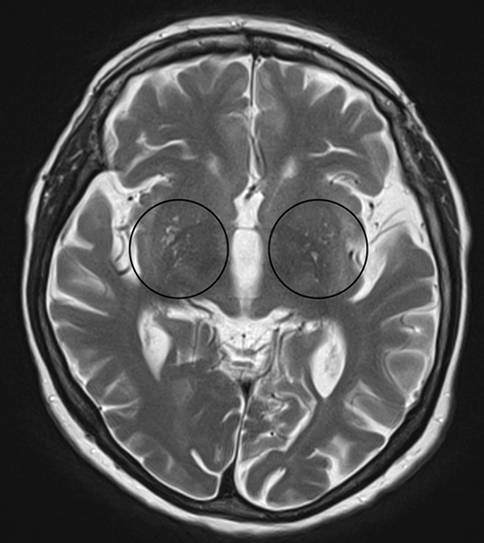

Lacunes and Virchow-Robin spaces

Lacunes are deep, small-vessel infarcts with a CSF-like signal on all MRI sequences (illustrated in Fig. 5). In contrast, Virchow-Robin spaces are enlarged perivascular spaces usually due to volume loss of the surrounding tissue with a predilection for the basal ganglia (illustrated in Fig. 6).

Fig. 6

Virchow-Robin spaces. Illustration of enlarged Virchow-Robin spaces (circles) in the lower aspect of the basal ganglia on both sides on axial T2-weighted images